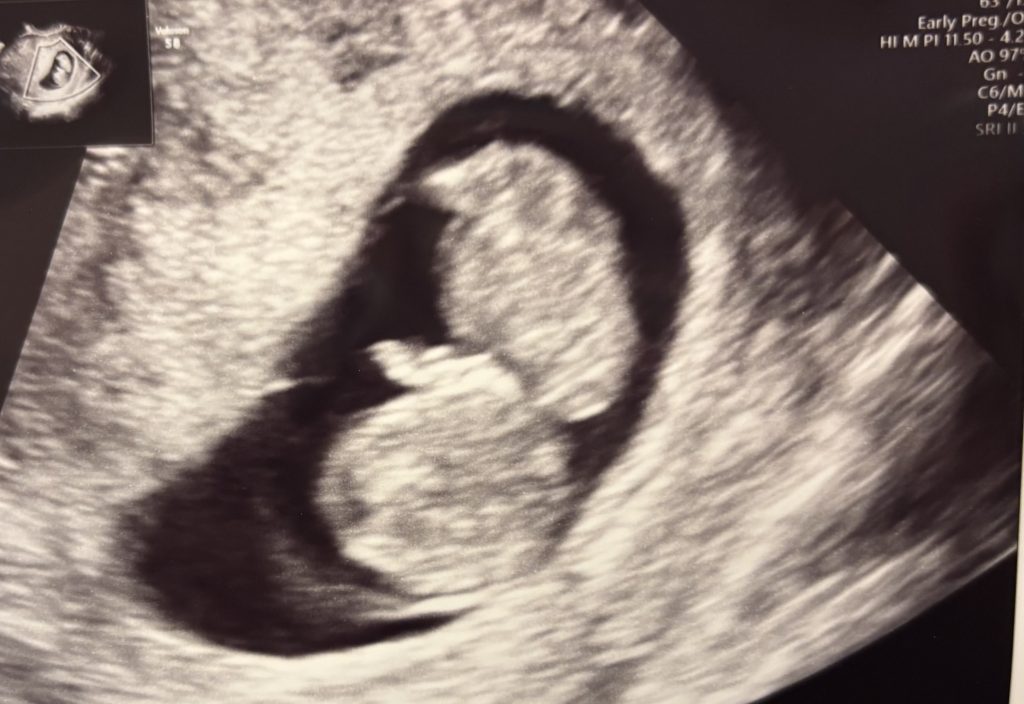

エコー写真(妊娠7週0日)

7週0日、前回とエコーの様子がまた変わっていました。

前回の卵黄嚢に加えて、赤ちゃんの体(胎芽)も確認できます。

心拍が聞こえたことと、赤ちゃんをエコーで確認出来たことで、前回よりも妊娠した実感が湧いてきました

エコー写真右下の数値の意味はこんな感じ。

CRL・・・頭の先からお尻までの長さ

Distance・・・胎嚢の大きさ

エコー写真の右下に表示されているCRLとは、頭の先からお尻まで長さです。

CRL5.6mm

1cmにも満たないのにしっかり命が芽生えているんだなと感動しました。

胎嚢の大きさですら18.7mm

2cm弱の小さな袋で妊娠の確認が出来るなんて、医療の技術はすごいなと思いました。

小さい胎芽がピコピコ動くのが、心拍とのことだったのですが、本当にわずかな動きすぎて、赤ちゃんの心臓が動いている、という感覚はまだ分かりませんでした、、(笑)